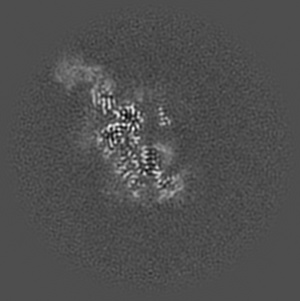

EMD-21256

BG505 SOSIP.v5.2 in complex with rabbit Fab 43A2

Single-particle3.52 Å

Sample: BG505 SOSIP.v5.2 in complex with rabbit Fab 43A2

HIV envelope trimer-elicited autologous neutralizing antibodies bind a region overlapping the N332 glycan supersite.